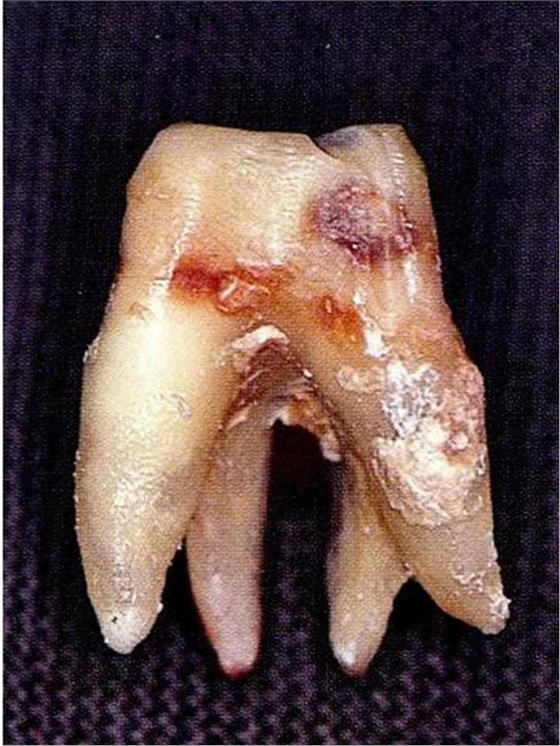

[多根分叉]

▼圖6-3上頜第一后磨牙的牙根形態(tài)異常。舌側(cè)面觀察。